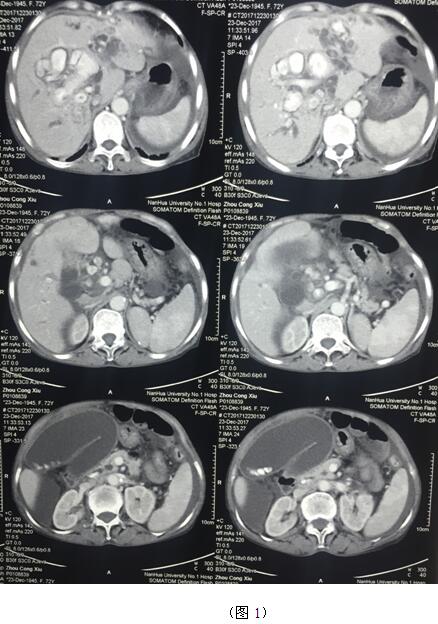

肝膽管結(jié)石疾病往往“鐘愛”貧困落后地區(qū)的病人,70多歲的周奶奶患全肝結(jié)石多年,由于家庭困難一直沒有得到有效治療,這個月病情惡化出現(xiàn)化膿性膽管炎并肝功能衰竭(圖1)。轉(zhuǎn)輾衡陽市內(nèi)多家醫(yī)院,不是因高昂的治療費用止步于院外,就是被以“病入膏肓”為由推脫出院。家屬經(jīng)過多方打聽得知衡陽市中心醫(yī)院是市里面的仁濟醫(yī)院,肝膽外科還是省級重點??疲覍偌安∪藨阎詈蟮南M麃淼搅酸t(yī)院肝膽外科。